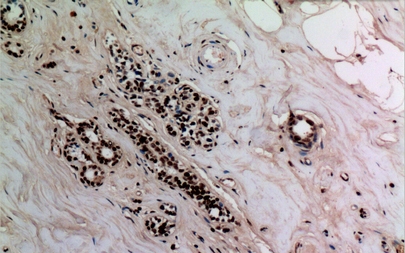

IHC (Immunohiostchemistry)

(Immunohistochemistry of paraffin-embedded Human breast tissue using NF?B-p65 (Acetyl Lys314/Lys315) Polyclonal Antibody at dilution of 1:100.)